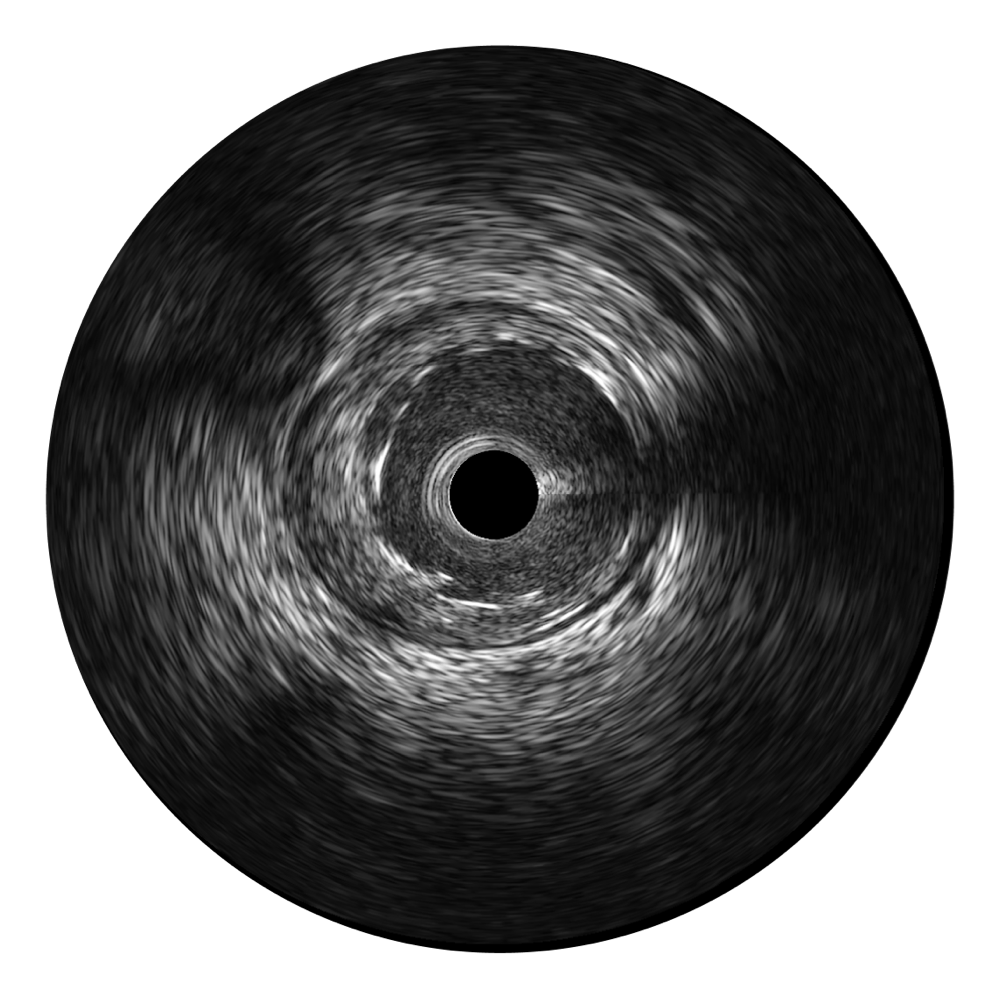

哈哈体育官网宽频IVUS图像

对比传统IVUS导管成像,哈哈体育官网宽频IVUS图像的近场支架梁显影更细腻,远场中膜外血管仍清晰可辨,兼顾远中近,兼顾分辨力与穿透深度